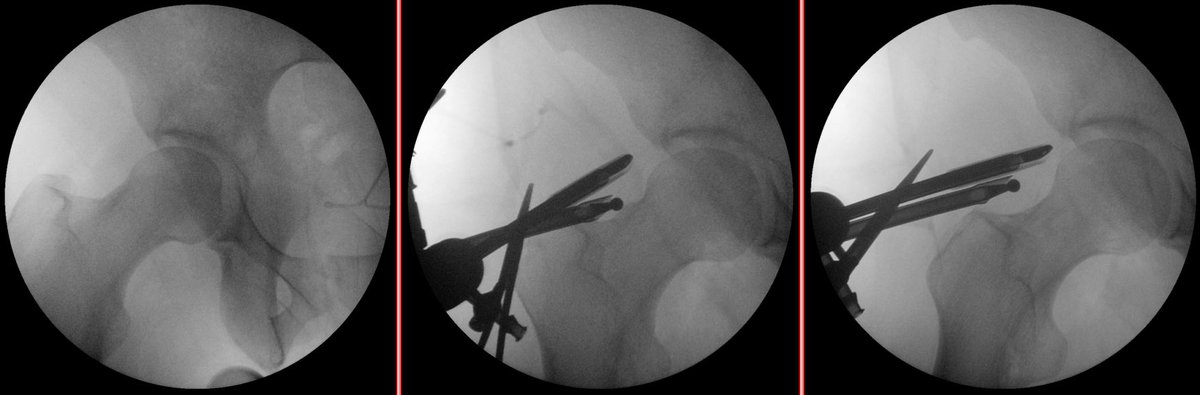

Future sports surgeon Dr. Nauert (PGY-5) presenting a case from the Krych service at conference this morning - a double level osteotomy for valgus deformity before ACL reconstruction #orthotwitter Dr. Aaron J. Krych